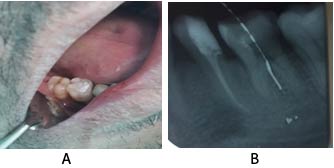

Upon examination the lower right first molar (46) had a very deep distal caries. The distal margin was too deep and there was a gingival overgrowth onto the distal cavity. The tooth was tender to vertical percussion. It was diagnosed as symptomatic  irreversible pulpitis with symptomatic  apical periodontitis (Figure 1).

Figure 1. Pre-operative view (A) and X-ray (B) of lower right first molar (the white line is an artifact).